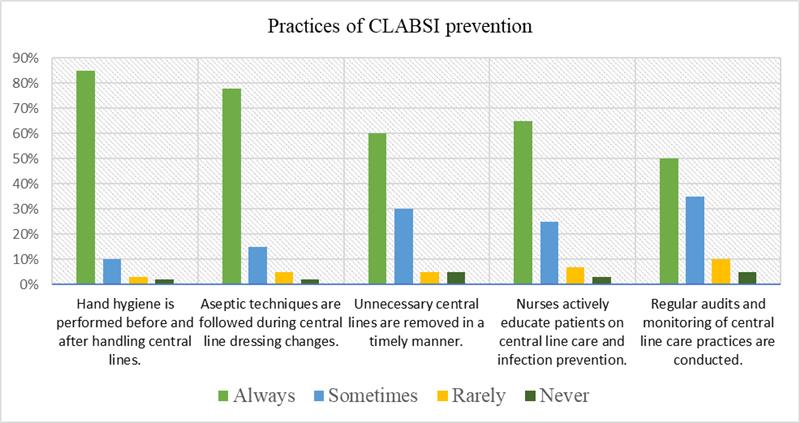

Knowledge and Practices of the Nurses Regarding Central Line Associated Infection at Tertiary Care Hospital, Peshawar, Pakistan

Background: Central Line-Associated Bloodstream Infections (CLABSIs) are a considerable source of increased mortality and morbidity during intensive care unit stays....Read More